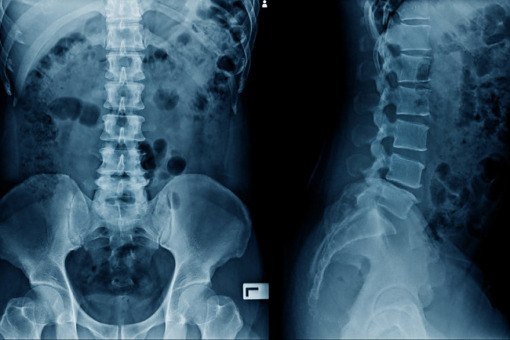

Według danych z literatury stawy odcinka szyjnego kręgosłupa są trzecim po stawach rąk i stóp obszarem najczęściej dotkniętym chorobą w przebiegu RZS. Zaobserwowano, że równowaga strzałkowa wpływa na jakość życia pacjentów i jest czynnikiem prognostycznym w zakresie efektów zabiegów chirurgicznych.

Równowaga strzałkowa jest jednym z zagadnień, które w ostatnim czasie przyczyniły się do pogłębienia zrozumienia patologii kręgosłupa. W przypadku RZS równowaga strzałkowa ma szczególne znaczenie ze względu na charakter schorzenia, które w naturalny sposób prowadzi do uszkodzenia fizjologicznych stabilizatorów stawów. Stawy uszkodzone stają się podatne na zaburzenia równowagi biomechanicznej. Proces destrukcji w stawach może przebiegać bezobjawowo lub objawiać się silnym bólem. Zaburzenia neurologiczne występują u 7–35 proc. pacjentów.

Poważnym problemem jest postępowanie z chorymi na RZS z niestabilnością odcinka szyjnego kręgosłupa. W piśmiennictwie niewiele uwagi poświęca się równowadze strzałkowej u chorych na RZS. Podkreśla się jednak znaczenie zabiegów chirurgicznych wykonywanych w celach profilaktycznych przed wystąpieniem ubytków neurologicznych. Całkowita ocena orientacji przestrzennej czaszki, parametrów ustawienia kręgosłupa szyjnego oraz równowagi strzałkowej jest ważnym elementem planowania operacji w niestabilności kręgosłupa szyjnego u chorych na RZS.